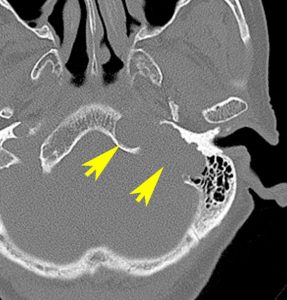

症例:小脳延髄角槽のもの,頸静脈孔へ少し入るもの

30歳くらいの女性に発生した無症状のものです。矢印のように拡大した頸静脈孔へ少し入っています。定位照射でもよかったかもしれませんが,若い女性なので手術しました。

脳槽部迷走神経根から発生したと考えて,外側後頭下開頭で摘出しましたが,予想外に延髄に近い部分の迷走神経から剥がせず,ほんの少し神経根の上に残しました。術後10年経ちますが腫瘍再燃はありません。聴神経腫瘍で顔面神経の上に薄く腫瘍を残すのと同じ考え方です。